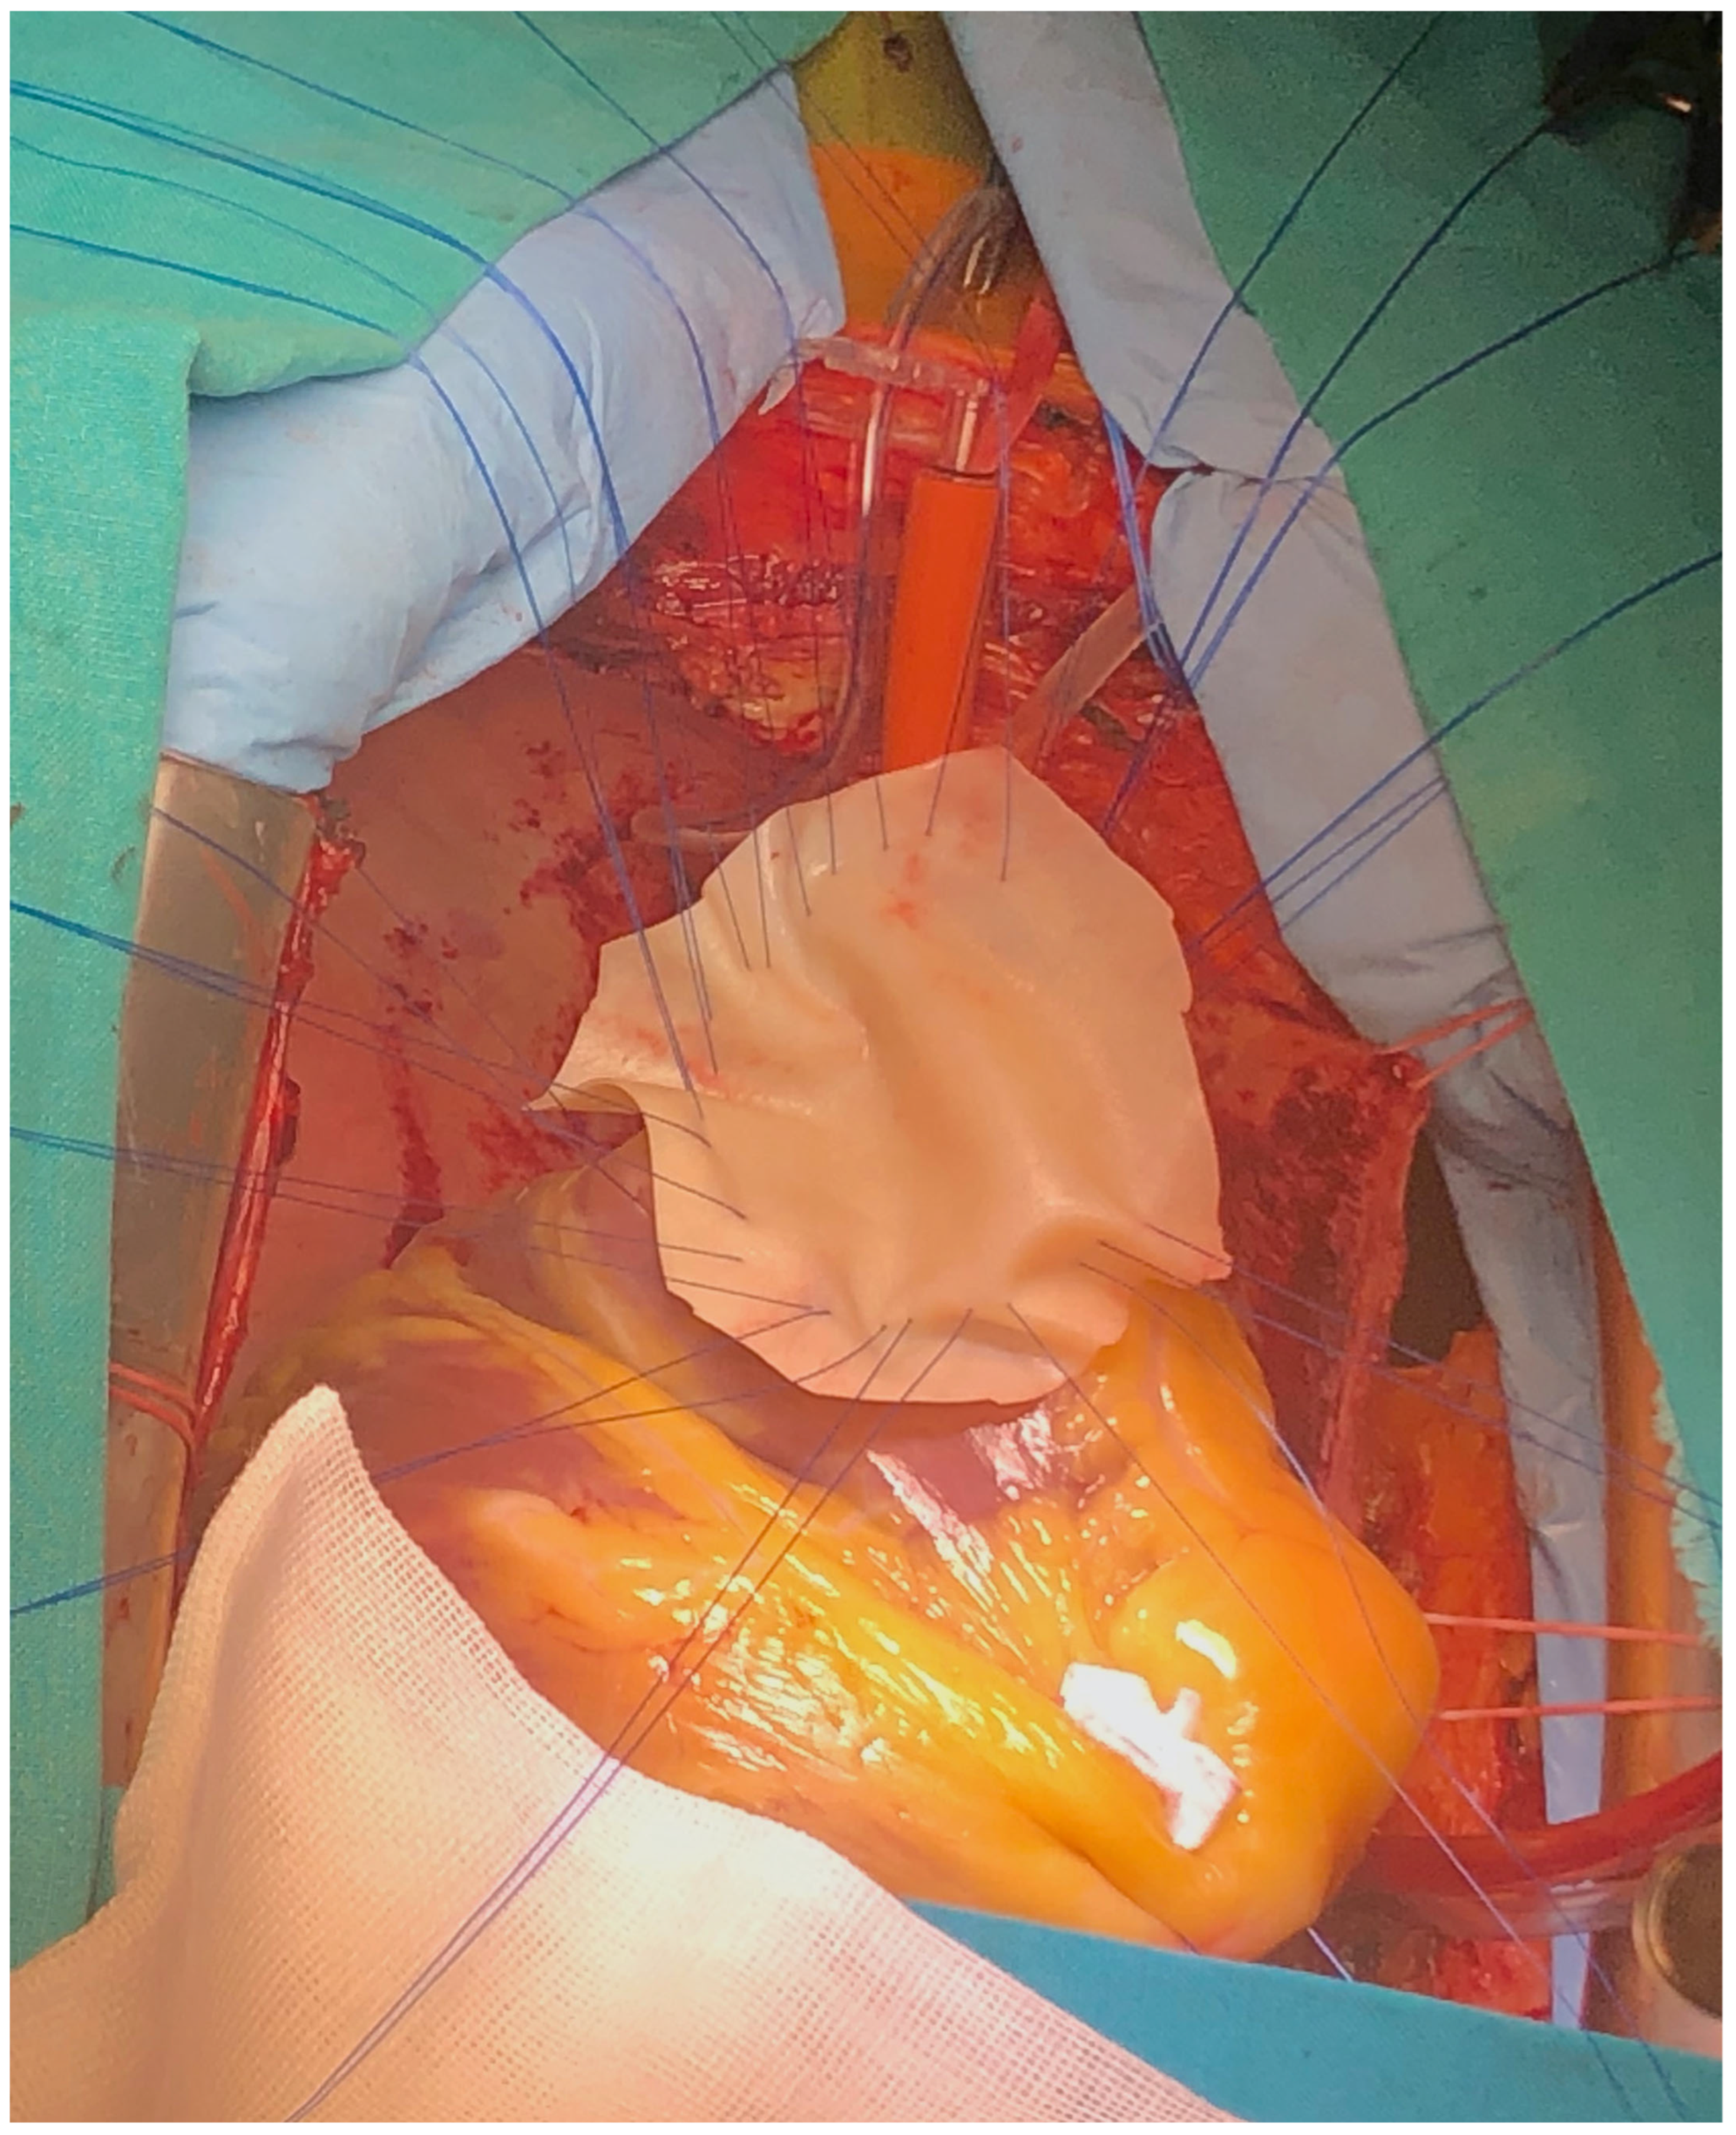

Figure 5. Surgical technique detail—exposure of VSD.

The surgery was carried out under general anesthesia, with iv induction and inhaled sevoflurane maintenance and total iv anesthesia during CPB. After median sternotomy, bicaval CPB was started, and the heart was arrested using anterograde and retrograde cold blood cardioplegia. After snaring both venae cava, the heart was enucleated with a 3.0 polypropylene stitch at the apex. A 10 cm incision was made on the posterior surface of the left ventricle, 2 mm parallel to the posterior interventricular artery. The margins of the VSD were identified. Interrupted matrass sutures of 2.0 Tevdek were placed circumferentially around the defect and used to secure a 4 × 7 cm bovine pericardial patch. The posterior papillary muscle was retracted into the sutures, so the mitral valve was replaced with a 27 biological prosthesis with preservation of the sub-valvular apparatus. The left ventriculotomy was closed with a double layer surjet suture, reinforced with Teflon felts. Details with surgical technique are shown in Figure 5, Figure 6, Figure 7 and Figure 8.